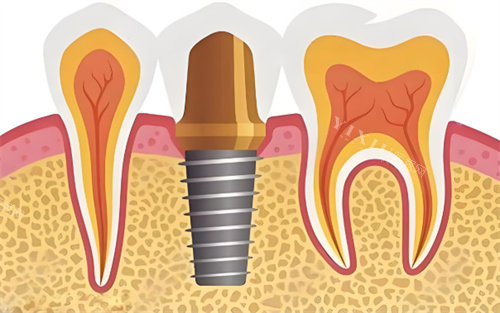

种植修复类

韩国进口种植体:4980元/颗起

瑞士ITI种植系统:12800元/颗起

全口半固定种植修复:68000元起

即刻负重种植术:15800元/颗起

骨增量手术(上颌窦提升):4500元起